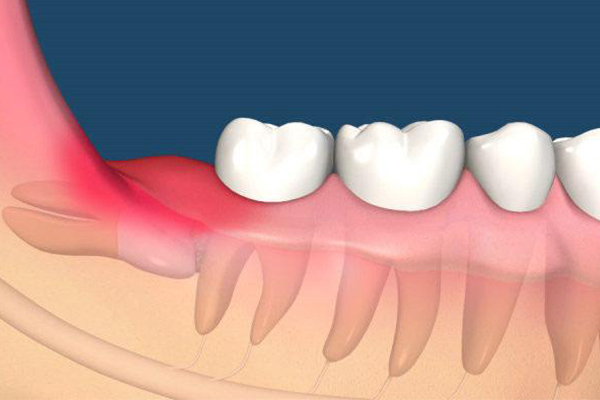

解答:智齿是指人的第三磨牙,是生长最晚的牙齿,靠近牙床的最后,大约16-30岁才会陆续的开始长出,也被人称为“智慧牙”,因为这时候的人已经心智成熟,但是智齿并非每个人都会长,最初是原始人用来咀嚼树根树皮的。

人的牙齿除了门牙,犬牙和磨牙之外,剩下的臼齿就是智齿,智齿一般是在9岁才开始形成,在14岁才长出齿冠,之后会慢慢的突破牙床,才能完整的长出来。但是很多人会出现智齿发炎的情况,因为随着人体的进化,牙弓越来越小,智齿的位置已经快没有了,所以生长出来的时候,会出现肿胀痛疼的感觉。

4. 阻生牙:一般是埋藏在牙床中,这也是最难弄的一种情况,一般疼痛的时候,就是病发,就必须拔除了。